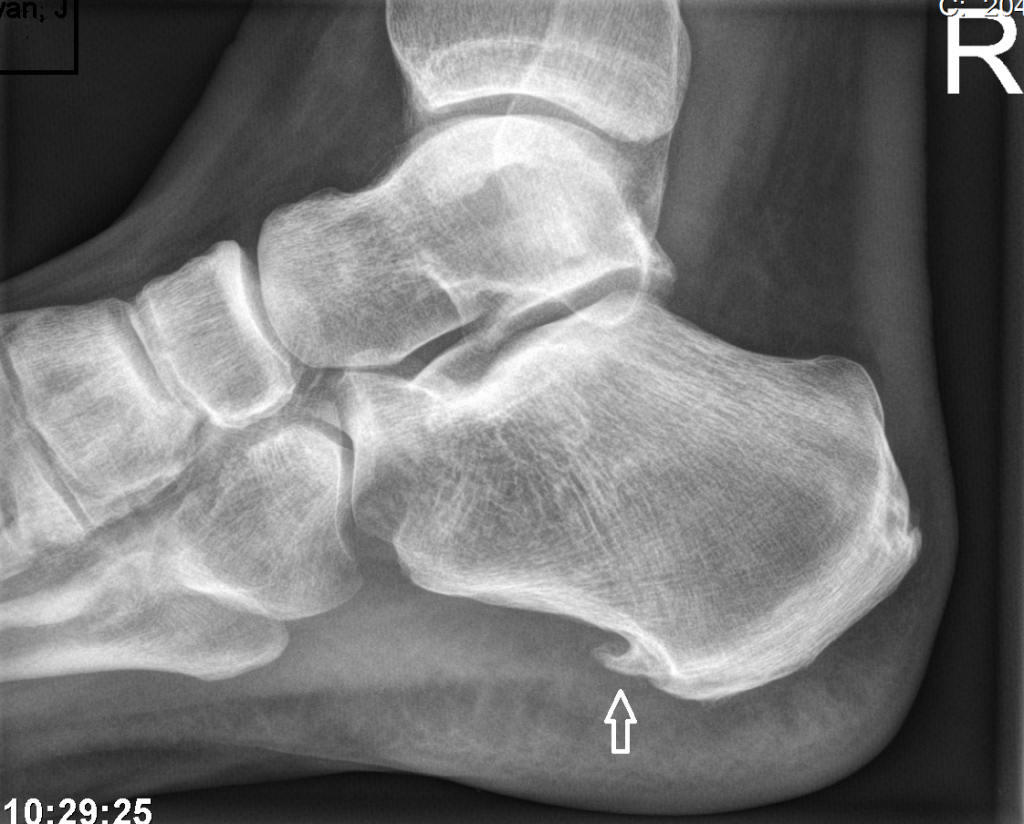

Onder uw voet zit een brede pees. De pees zit tussen de hiel en de tenen (zie afbeelding onder). Deze pees kan overbelast raken, om de voet te beschermen tegen overmatige druk, maakt het lichaam een hielspoor aan. Een hielspoor is dus een versteviging van de aanhechting van de het peesblad.

De plek waar de peesplaat aan de onderkant van de hiel vastzit, kan pijn doen. Als deze peesaanhechting overbelast is, kan er zich een hielspoor vormen. Een hielspoor is een benige versteviging van de peesplaat onder de voet. het lichaam creëert deze verbening om verdere schade van de pees te voorkomen.

Afbeelding boven: Geïrriteerde peesplaat (fasciitis plantaris). Het lichaam kan hier een hielspoor bouwen om de pees te versterken. Hieronder ziet u een hielspoor.